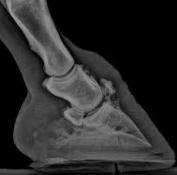

長骨の関節軟骨には常に病変が生じます。これは骨端における強力な破骨作用の結果であって、骨端の骨質のみでなく、関節軟骨の深部にある石灰化された層もまた破壊される。

関節軟骨は薄くなり、その圧迫された表面には変性と糜爛(erosion)が生じます。